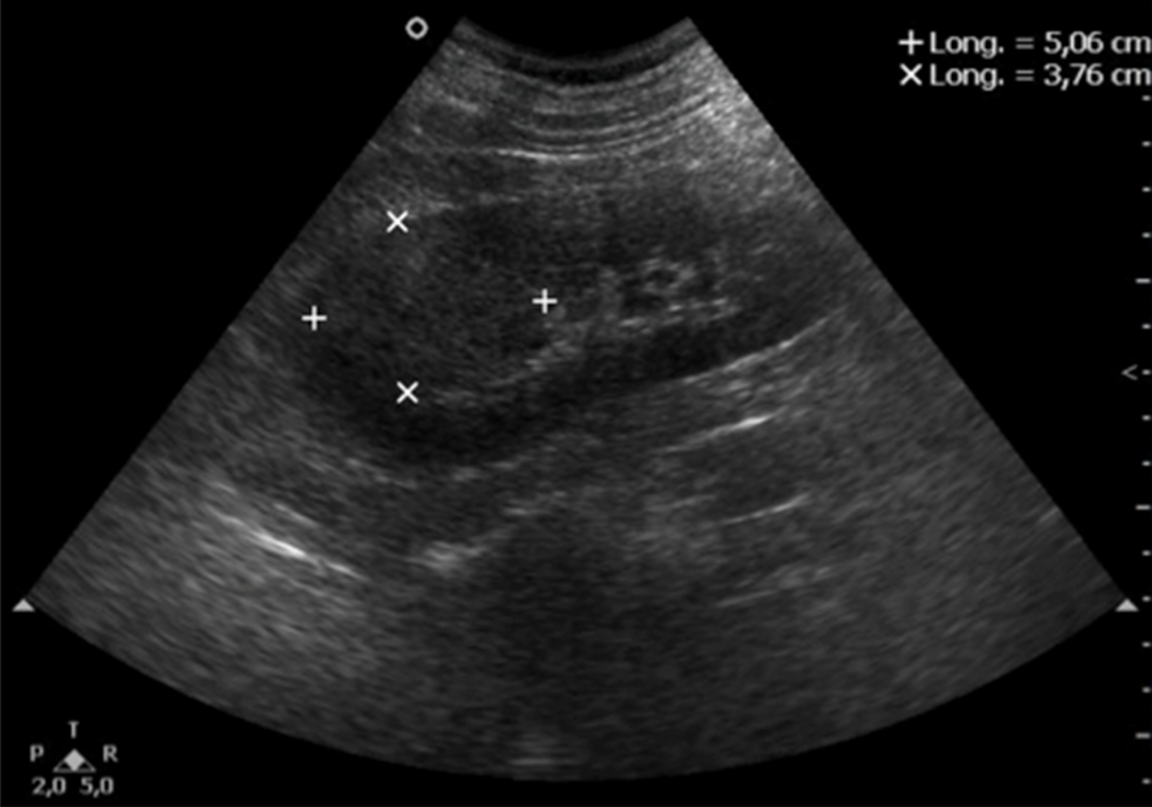

10. kép:

Vese daganat

A vese daganatok sokszor nehezen észrevehetőek ultrahangal, mert a megjelenésük bizonyos esetekben nagyon hasonlít a vese normális állományára. Ebben az esetben a jelölések mutatják a daganat határait. Támpontot ad a diagnózisban hogy a vese kontúrját az eltérés kidomborítja, illetve a vese üregrendszere felé is bedombrodik az elváltozás.